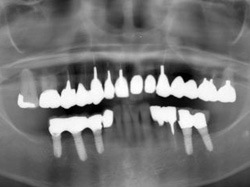

両側5歯症例

両側5歯症例両側5歯症例両側5歯症例 主訴-義歯のバネが壊れて手前の歯が痛んできた。 術前(旧義歯装着、鏡像) 術前(下顎粘膜面、鏡像)術前(下顎粘膜面、鏡像)術前(下顎粘膜面、鏡像) 術前レントゲン術前レントゲン術前レントゲン 術前口腔内(正面観)術前口腔内(正面観)術前口腔内(正面観)

術後(鏡像)術後(鏡像)術後(鏡像) 術後口腔内(正面観)術後口腔内(正面観)術後口腔内(正面観)もう入れ歯は要らなくなりました。 術後レントゲン術後レントゲン術後レントゲン